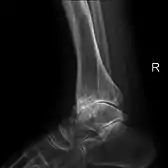

Lateral X-ray scan of ankle with secondary osteoarthritis

Lateral

Frontal X-ray scan of ankle with secondary osteoarthritis

Frontal

Secondary osteoarthritis of the ankle (due to an old bone fracture) in an 82-year-old woman